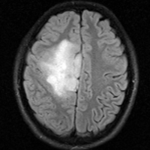

This is a classic case of a multi-sequence MRI exam we wish to spatially align to the anatomical reference scan (T1-SPGR). The scan of interest is the DTI image to be aligned for surgical planning/reference. The key points are: 1) the DWI sequence (EPI) contains distortions we seek to correct via non-rigid alignment; 2) the DTI baseline is similar in contrast to a T2, albeit at much lower resolution, but we do not have a T2 weighted anatomical scan, but instead a T1 and a FLAIR. So we use the FLAIR as the fixed image, because its contrast matches the DTI-baseline better than the T1, esp. in terms of tumor contrast.

• a direct registration of the DTI_baseline to the T1 is not recommended, since the FLAIR is a better match in contrast to the DTI baseline. We therefore first align the DTI with the FLAIR and then also register the T1 to the FLAIR. This minimizes resampling to only 1 image and only 1 transform.

• the DTI-FLAIR registration includes non-rigid deformation to correct for the strong distortions from the EPI acquisition. Because of the nonrigid component a mask of the brain parenchyma helps in obtaining a meaningful transform. Registration without a mask is possible but not as good as with a mask.

RegLib C27 Result1.gif original and registered pair of FLAIR and DTI (click to enlarge)

RegLib C27 Result2.gif original and registered pair of T1 and DTI (click to enlarge)